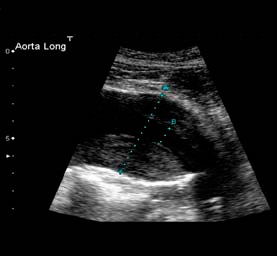

Ο γιατρός μπορεί να ανακαλύψει το ανεύρυσμα της κοιλιακής αορτής σε μια κλινική εξέταση ρουτίνας. Η ψηλάφηση σφύζουσας μάζας στην κοιλιακή χώρα θέτει την υπόνοια του ανευρύσματος της κοιλιακής αορτής. Η διαγνωστική προσέγγιση γίνεται εύκολα με υπερηχογράφημα κοιλίας, εξέταση απλή και ανώδυνη.

Το μέγεθος, η θέση του ανευρύσματος και η γενική κατάσταση του ασθενή καθορίζει το πώς αυτό πρέπει να αντιμετωπιστεί. Όταν το ανεύρυσμα είναι μικρό, ο γιατρός συνήθως συστήνει περιοδικά τον έλεγχο της διαμέτρου του ανευρύσματος, είτε με υπερηχογράφημα είτε με αξονική τομογραφία. Όταν η διάμετρος του ανευρύσματος είναι μεγαλύτερη από 5 εκατοστά ή αυτό αυξάνει ταχέως σε διάμετρο, τότε απαιτείται επεμβατική θεραπεία.